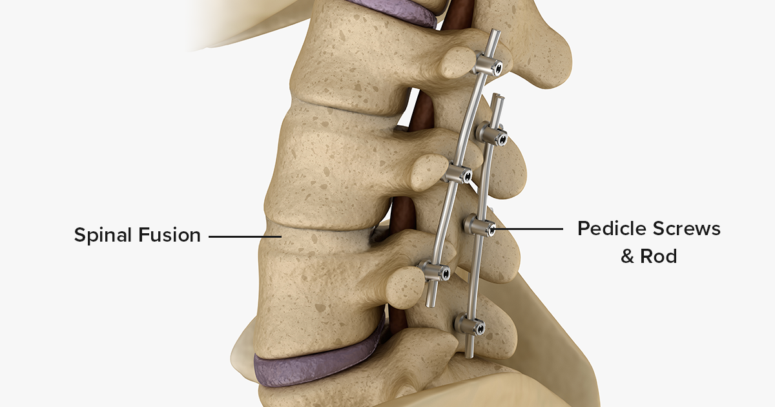

Surgery is rarely required for ankylosing spondylitis, but may be considered if there is severe joint damage, spinal deformity, or nerve compression. Options include:

Corrective spinal surgery – In selected cases with significant deformity affecting function or quality of life.